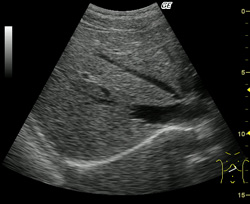

腹部エコーとは

腹部エコー(腹部超音波検査)とは、腹部に超音波を発信して腹腔内の臓器から返ってくる反射波を受信し、腹腔内を画像化して診断する検査です。腹部エコーの需要は非常に高く、腹部エコーを行っている医院は患者さんの訪院件数が非常に多いということが知られています。現在の問題点としては、検査項目が多いことや技師の不足によって患者さんが他の医院に流出しやすいということが挙げられます。

腹部エコーでわかる病気

肝硬変

脂肪肝

胆石

がん etc・・・